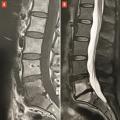

La plupart des rhumatologues français réalisent les injections de corticostéroïdes dans les articulations interapophysaires postérieures pour passer un cap douloureux aigu, dans les cas où l’examen clinique ou la ­présence d’un hypersignal « œdémateux » en IRM, sur les séquences ­pondérées en T2 avec suppression du signal de la graisse (fig. 4), suggè­rent qu’elles peuvent être en partie responsables des douleurs. Cependant, des essais randomisés n’ont pas pu mettre en évidence de supériorité des injections de corticoïdes dans les articulations postérieures, par rapport à des injections intra-arti­culaires de sérum salé.10, 11 Par ailleurs, il n’y a pas de place, d’une façon générale, pour un geste percutané intradiscal dans les lombalgies chroniques communes, car leur cause est multifactorielle et toujours incertaine.

Le cas des discopathies dégénératives dites « actives », avec un signal « œdémateux » (hypersignal T2) des plateaux vertébraux en IRM (« Modic 1 ») est particulier (fig. 4). C’est le seul signe radiologique qui soit bien corrélé aux lombalgies. D’où la tentation de traiter les patients par des injections locales de corticoïdes.12 Un essai randomisé chez des lombalgiques exprimant un signe de « Modic 1 » a montré que l’efficacité d’une injection intradiscale de corticoïdes, sur la lombalgie, est supérieure à celle d’une injection intradiscale de sérum salé à un mois (-2,4/10 points sur une échelle visuelle analogique douleur), mais pas à trois mois ou ultérieurement.13 Ce bénéfice paraît trop éphémère pour justifier l’usage de cette voie d’administration, qui comporte un risque, faible mais ­certain, de spondylodiscite infectieuse iatrogène. Dans cette situation, il paraît plus raisonnable de se limiter à des injections épidurales locales de corticoïdes ou à une faible corti­co­thérapie per os.